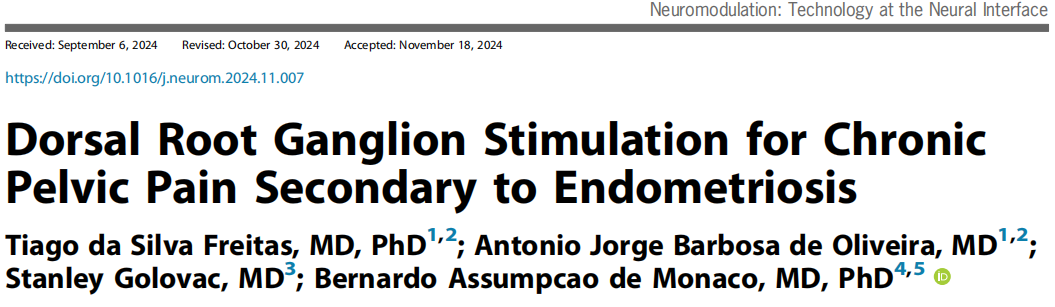

L1和S2中DRG电极的植入位置

背根神经节刺激(DRG-S)手术分为两个阶段,针对双侧L1和S2背根神经节。第一阶段为测试,设置传统参数(脉冲宽度200-300μs,频率20 Hz,振幅70%-80%的痛觉阈值,通常在0.2-0.8 mA之间),并于第4天和第7天评估。若患者疼痛改善≥50%(VAS评分),则进入第二阶段,即永久植入DRG-S电极和植入式脉冲发生器于臀部。术后12个月随访,调整DRG参数以实现最佳效果。